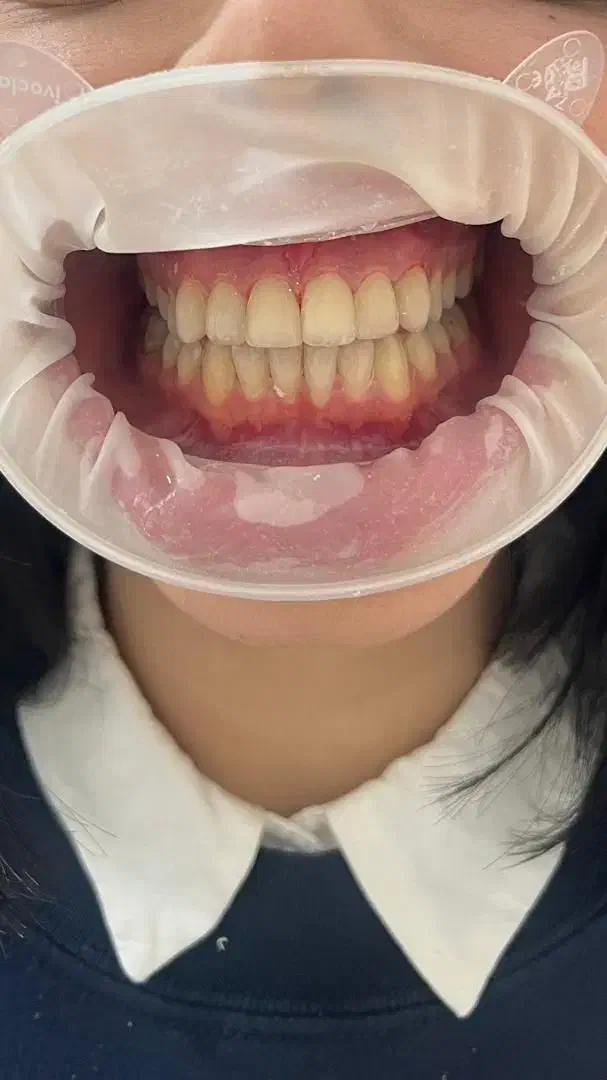

خدمات دندان پزشکی با متناسب شرایط و بودجه شما

ساعت فعالیت ۹صبح الی ۲۴ حتی روز های تعطیل و جمعه دندان پزشکی بزرگسال و اطفال با شش سال سابقه ی کاری طرف قرارداد با بیمه ی تکمیلی ( تامین اجتماعی البرز کوثر رازی ایران و معلم و دانا و آتیه سازان حافظ بانک کشاورزی و sos ) تعرفه برای مراجعین بدون بیمه تکمیلی جرم گیری ۹۰۰هزار تومان الی یک میلیون و دویست کشیدن ساده ۴۰۰الی ۷۰۰هزار تومان کشیدن دندان عقل ۹۰۰هزار تومان جراحی دندان ۱۶۰۰الی۱۸۰۰ جراحی دندان عقل ۱۸۰۰ الی ۲ ترمیم ۱۵۰۰ الی ۱۷۰۰ کامپوزیت ونیر از ۱۵۰۰ عصب کشی و ترمیم دندان ۲۷۰۰الی۳۹۰۰ روکش های معمولی ۳۴۰۰ روکش های سرامیک ۴۳۰۰ ایمپلنت با روکش ۱۵الی ۱۷میلیون کلیه خدمات دندان پزشکی مخصوص اطفال (عصب کشی ترمیم کشیدن جرم گیری روکش) شرایط اقساطی با دریافت چک صیاد امکان پذیر میباشد ادرس رشت گاز دروازه لاکان مسجد امیرالمومنین کوچه ی ۱۶متری سمیه جهت نوبت دهی در دیوار خدماتی ک درخواست دارین رو به همراه شماره تماس ارسال بفرمایید همه روزه حتی روز های تعطیل